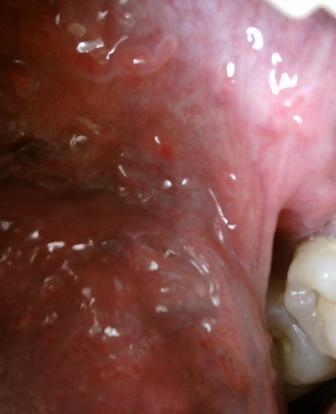

石家庄九州皮肤病医院 > 尖锐湿疣 > > > 外阴瘙痒是尖锐湿疣的前兆吗尖锐湿疣性病现在是比较多发的,相信大家现在对于尖锐湿疣性病已经不再陌生了,尖锐湿疣性病,发病部位是比较隐蔽的,一般常发部位是人类生殖器官周围,肛门周围以及口腔周围。尖锐湿疣也是会发病在阴道部位的。

外阴瘙痒是尖锐湿疣的前兆吗发病初期病情相对来说是比较轻微的,不会有什么异常反应和不适感,初期是治疗疾病的最佳时期,大家不要因为任何原因而耽误治疗,这样只会导致疾病加重,进而会导致疾病加重,不利于疾病的治疗。中医通常认为尖锐湿疣的发病原因,是由于患者的房事不洁或间接触污秽之物品所导致的,尖锐湿疣的发病原因有很多,因人而异。患病之后对因对症治疗才可以达到很好的治愈疾病的目的。

外阴瘙痒是尖锐湿疣的前兆吗早期的表现症状可能不是很明显。但是会出现灼痛、外阴瘙痒或性交后疼痛等不舒服症状。女性尖锐湿疣反复发作又难以控制,有时疼痛较严重等原因,造成病人思想负担过重,以上就是石家庄治疗尖锐湿疣的医院九洲皮肤病医院专家的观点,希望可以帮助到您,如有任何不理解的情随时拨打石家庄九洲尖锐湿疣医院康复热线:0311-89109686在这里石家庄九洲皮肤病医院全体医护人员祝愿广大患者朋友们可以早日康复。摆脱病魔。